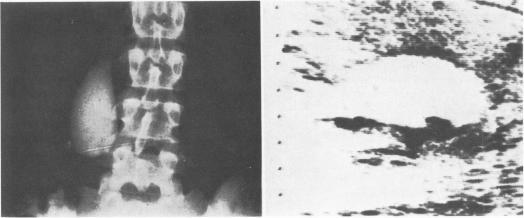

The gallbladder can be visualized by ultrasound (cholecystosonography) and gallstones seen as echo producing densities. Under cholecystosonographic observation the gallbladder can be demonstrated to contract following stimulation by cholecystokinin. This establishes patency of the cystic duct and excludes a diagnosis of acute obstructive cholecystopathy. The gallbladder has been identified in 84 of 86 patients. Stones have been identified sonographically in 64% of 42 patients with proven gallstones (75% of the last 20 cases). The gallbladder contracted following stimulation in 18 of 20 cases with a patent cystic duct. Cholecystosonography is simple, safe and economical. Cholecystonography with cholecystokinin stimulation is the first diagnostic study to be performed when cholecystolithiasis is suspected and the following circumstances exists: a) an acute right upper quadrant (RUQ) syndrome consistant with acute obstructive cholecystopathy. b) cholestasis or hepatic dysfunction. c) a history of allergy to contrast media. Cholecystosonography may detect gallstones in a gallbladder visualized by oral cholangiography when stones are of the same density as the contrast media.